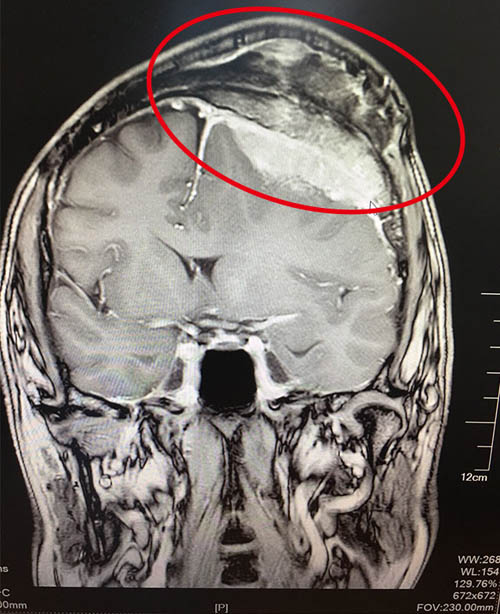

2、CT掃描:在腦膜瘤的診斷上,CT掃描已取代同位素腦掃描、氣腦和腦室造影、腦膜瘤多為實(shí)質(zhì)性且富于血運(yùn),適合于CT檢查,其準(zhǔn)確性能夠達(dá)到發(fā)現(xiàn)1cm大小的腦膜瘤。在CT掃描圖像上,腦膜瘤有其特殊征象,在顱內(nèi)顯示出局限性圓形密度均勻一致的造影劑增強(qiáng)影像,可并有骨質(zhì)增生,腫瘤周邊出現(xiàn)密度減低的腦水腫帶,相應(yīng)的腦移位,以及腦脊液循環(huán)梗阻引起的腦積水征象。